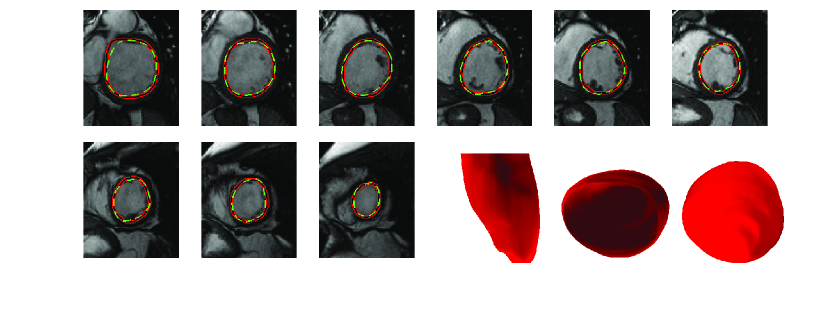

Fig. 9 illustrates the automatic and manual segmentation results of the LV for a typical cardiac MRI dataset from the base to the apex and three views of the reconstructed LV chamber (front, base and apex views). Also, segmentation results for image slices at the apex and mid LV, which are generally complex due to presence of papillary muscles and low resolution, are depicted in Fig. 10. In the figures, automatic segmentation results are shown in red. The ground truth manual segmentations drawn by experts are shown in green for comparison. Automatic and manual segmentation results for multiple datasets of the MICCAI database (Radau et al., 2009) are illustrated in Fig. 11. In the figure, each row corresponds to one patient/dataset which includes normal subjects (SC-N) and the ones with ischemic heart failure (SC-HF-I), non-ischemic heart failure (SC-HF-NI) and LV hypertrophy (SC-HYP).

From Figs. 9-11, it can be seen that the LV was accurately segmented from the base to the apex. The alignment process resulted in a smooth 3D reconstruction of the LV in Fig. 9. The first image on the left corner of Fig. 9 shows a slight leakage from the ground truth. This situation is one of the challenging cases that, due to the fuzziness of the LV border, contours tend to leak to surrounding tissues in pure deformable models. Luckily, by integrating the inferred shape into the deformable models, this leakage was significantly prevented in this image and also all similar cases in the dataset such as the first and second images in the fifth row of Fig. 11. In other challenging cases, such as in Fig. 10, that pure deformable models tend to shrink inward due to the presence of papillary muscles, or leak outward due to low resolution and small contrast of images at the apex, our method overcame these shortcomings.